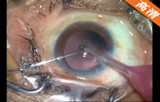

2.2mm微切口白内障超声乳化+人工晶体植入手术

该手术做2.2mm角巩膜缘主切口及侧切口; 前房注入医用透明质酸钠; 连续环形撕囊; 水分离、水分层;超声乳化核和核壳 ,注吸皮质; 抛光前囊和后囊; 前房及囊袋内注入透明质酸钠凝胶; 植入折叠人工晶体; 吸除透明质酸钠凝胶; 水密切口。

关键词: 2.2mm微切口 白内障 超声乳化 折叠人工晶体